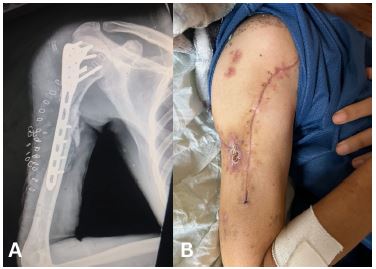

Case 2

A 43-year-old male presented with multiple injuries sustained from a bomb explosion. He had a head injury and a Glasgow Coma Scale (GCS) score of 8, a chest injury with haemopneumothorax, and a Gustilo-Anderson Grade IIIB open fracture of the right proximal humerus with no signs of neurovascular injury of the right upper limb. He was intubated in the ED and subsequently underwent a craniotomy, bilateral intercostal chest tube insertions, and Open Reduction Internal Fixation (ORIF) of the humerus. This ORIF failed due to an inappropriate plate length and was later revised on another occasion with the correct plate followed by soft tissue repair and covering of the bone and plate with a SSG. The intercostal tube was removed after 6 days. He was admitted to the Intensive Care Unit (ICU) for 4 weeks after which weaning from mechanical ventilation was successful and he was transferred to a normal word.

Images are Not Display Check it

Figure 2: (A) Anteroposterior view radiograph of the fracture and internal fixation. (B) Clinical photograph of the healed wound.